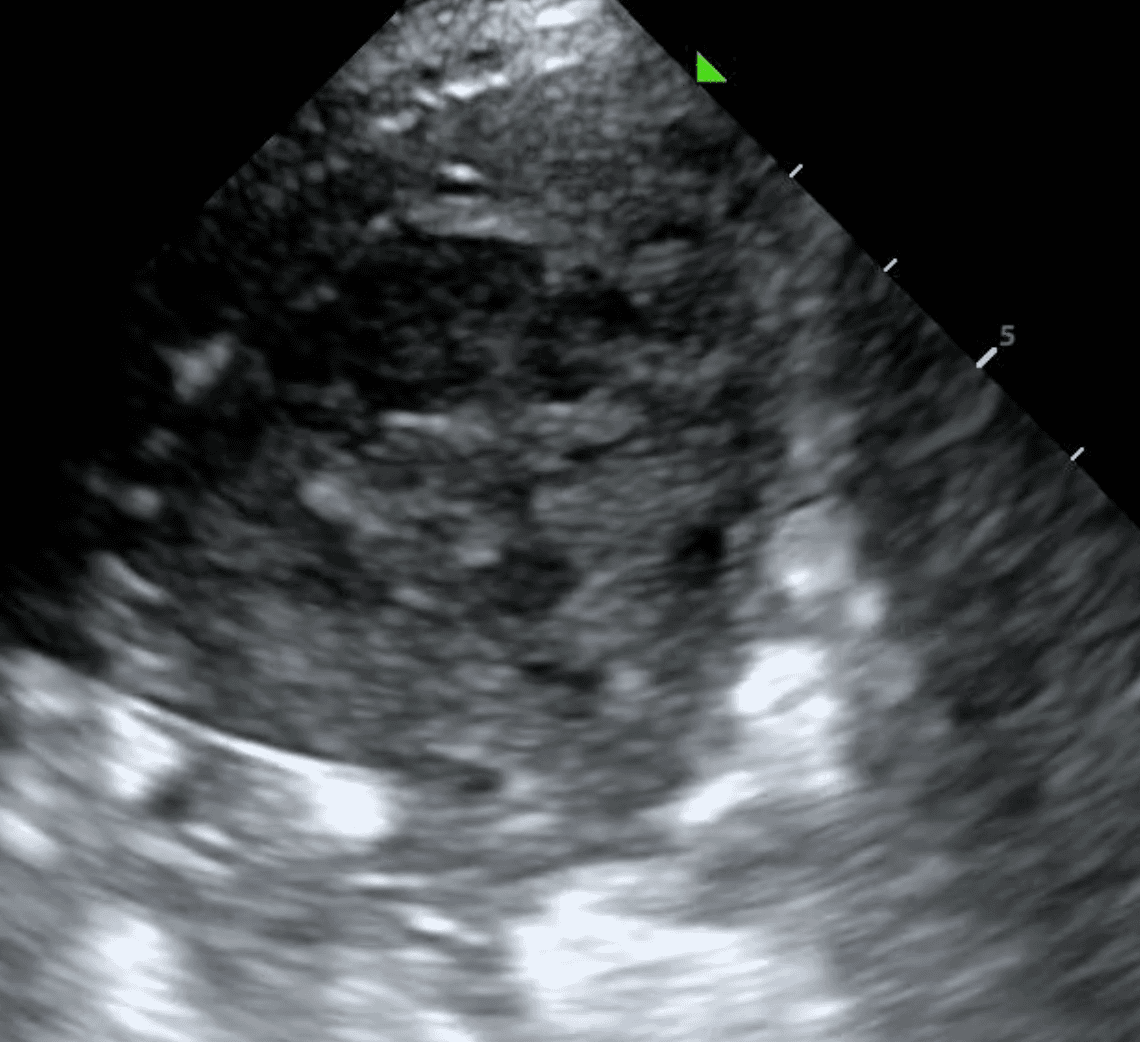

Cavitary lesions are characteristics of advanced TB disease. They can reflect lung abscess, nodules or granulomas. Cavitary lesions have two distinct characteristics:

The cavity appears hypoechoic (darker) compared to the surrounding lung tissue due to the presence of fluid, pus or debris.

The margins of the cavity may appear irregular or poorly defined on ultrasound, reflecting its inflammatory nature.